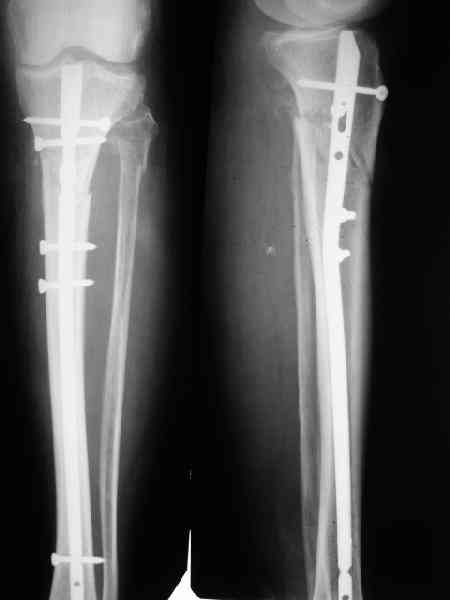

Как обещал, выкладываю рентгенограммы нашего пациента.

Пациенту М., 30-ти лет, 1,5 года назад в одной из московских больниц был выполнен остеосинтез бедренной кости штифтом UFN (диаметр штифта 9 мм).

К нам больной поступил с признаками ложного сустава бедренной кости, перелома

штифта и дистального блокирующего винта (images 1,2,3).

27 марта выполнено удаление блокирующих винтов (сломанный винт пришлось высверливать цапфен-бором), сломанного штифта (дистальный фрагмент удален через канал, образованный разверткой из коленного сустава - image 4),

рассверливание костно-мозгового канала, реостеосинтез штифтом UFN (при проведении штифта в дистальном отломке мы использовали поляризующий винт, диаметр штифта 10 мм). После операции в связи гемартрозом дважды (на 1 и 3 сутки) выполняли пункцию коленного сустава. Сейчас признаков скопления жидкости в полости сустава нет. Послеоперационные рентгенограммы - images 5, 6, 7.